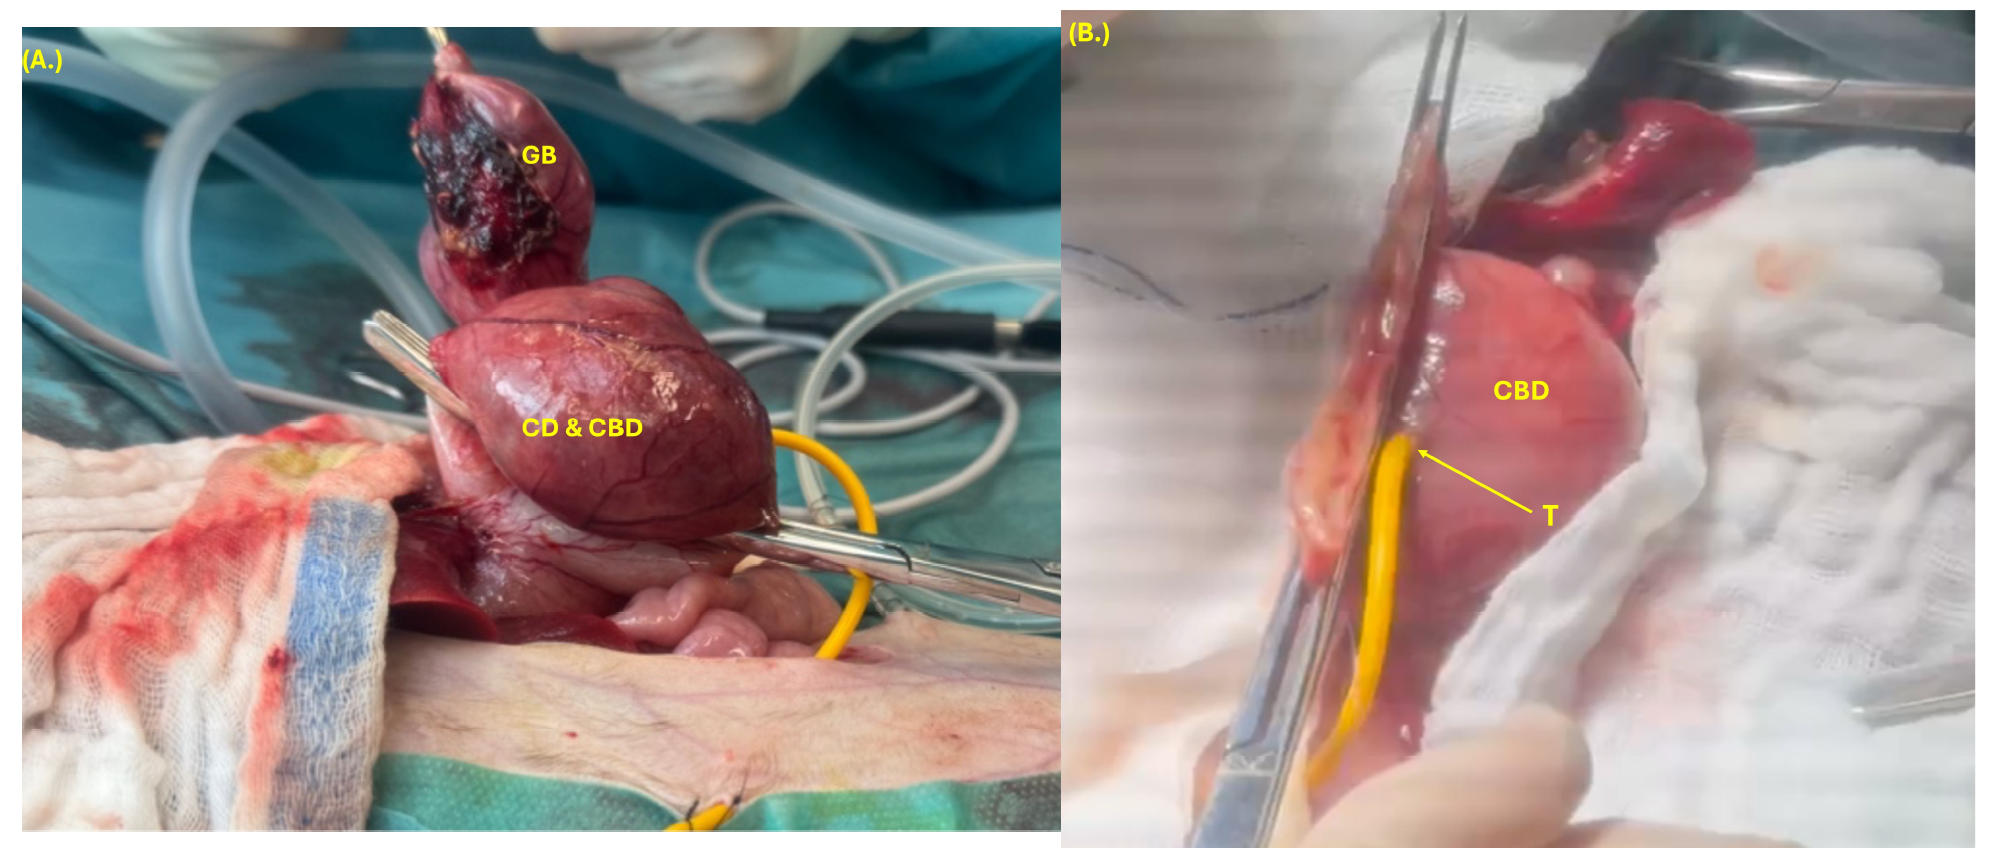

为了对胆总管进行导管化,进行了十二指肠切开术,但由于十二指肠乳头完全不可逆地阻塞,这一操作无法完成。尽管胆总管被阻塞,但主胰管仍然通畅,可以进行冲洗。进行了胆囊切除术,并使用4-0缝线以双层连续缝合模式(先对合缝合,后Cushing缝合)关闭了通向胆总管的开口(下图)。

↑ 胆囊切除术(A)涉及胆囊(GB)、胆囊管(CD)及部分扩张的胆总管(CBD),胆囊切除术后采用双层缝合关闭胆总管(CBD),并在扩张的胆总管内放置胆道造口管(T)。